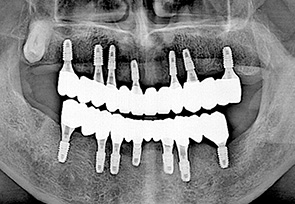

전악 임플란트는 치아가 완전히 없는 상태라도 잇몸뼈가 남아 있다면 임플란트를 여러개 심어 고정식으로 이를 해 넣을 수 있습니다. 잇몸 뼈에 단단히 고정되는 임플란트를 이용한 치료법으로 틀니를 사용할 때 보다 힘이 훨씬 좋고 내 치아 처럼 사용할 수 있습니다. 자연치아는 모두 28개 이지만 실직적으로 자연치아 개수만큼 다 심을 필요는 없습니다. 고정성 전악 임플란트를 위해서는 위 아래 턱 뼈와 맞물리게 되는 치아의 상태와 잇몸 뼈의 상태 등을 고려하여 임플란트를 식립하게 되며 보통 아래는 6~7개, 위에는 7~8개의 임플란트를 식립한 후 고정식으로 보철물을 결합하게 됩니다.

치료 케이스 보기

• after